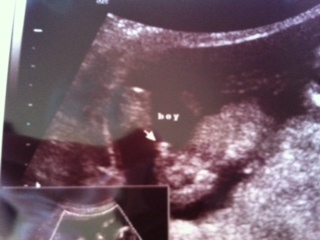

and here is the nub shot

That 3rd pic looks great.